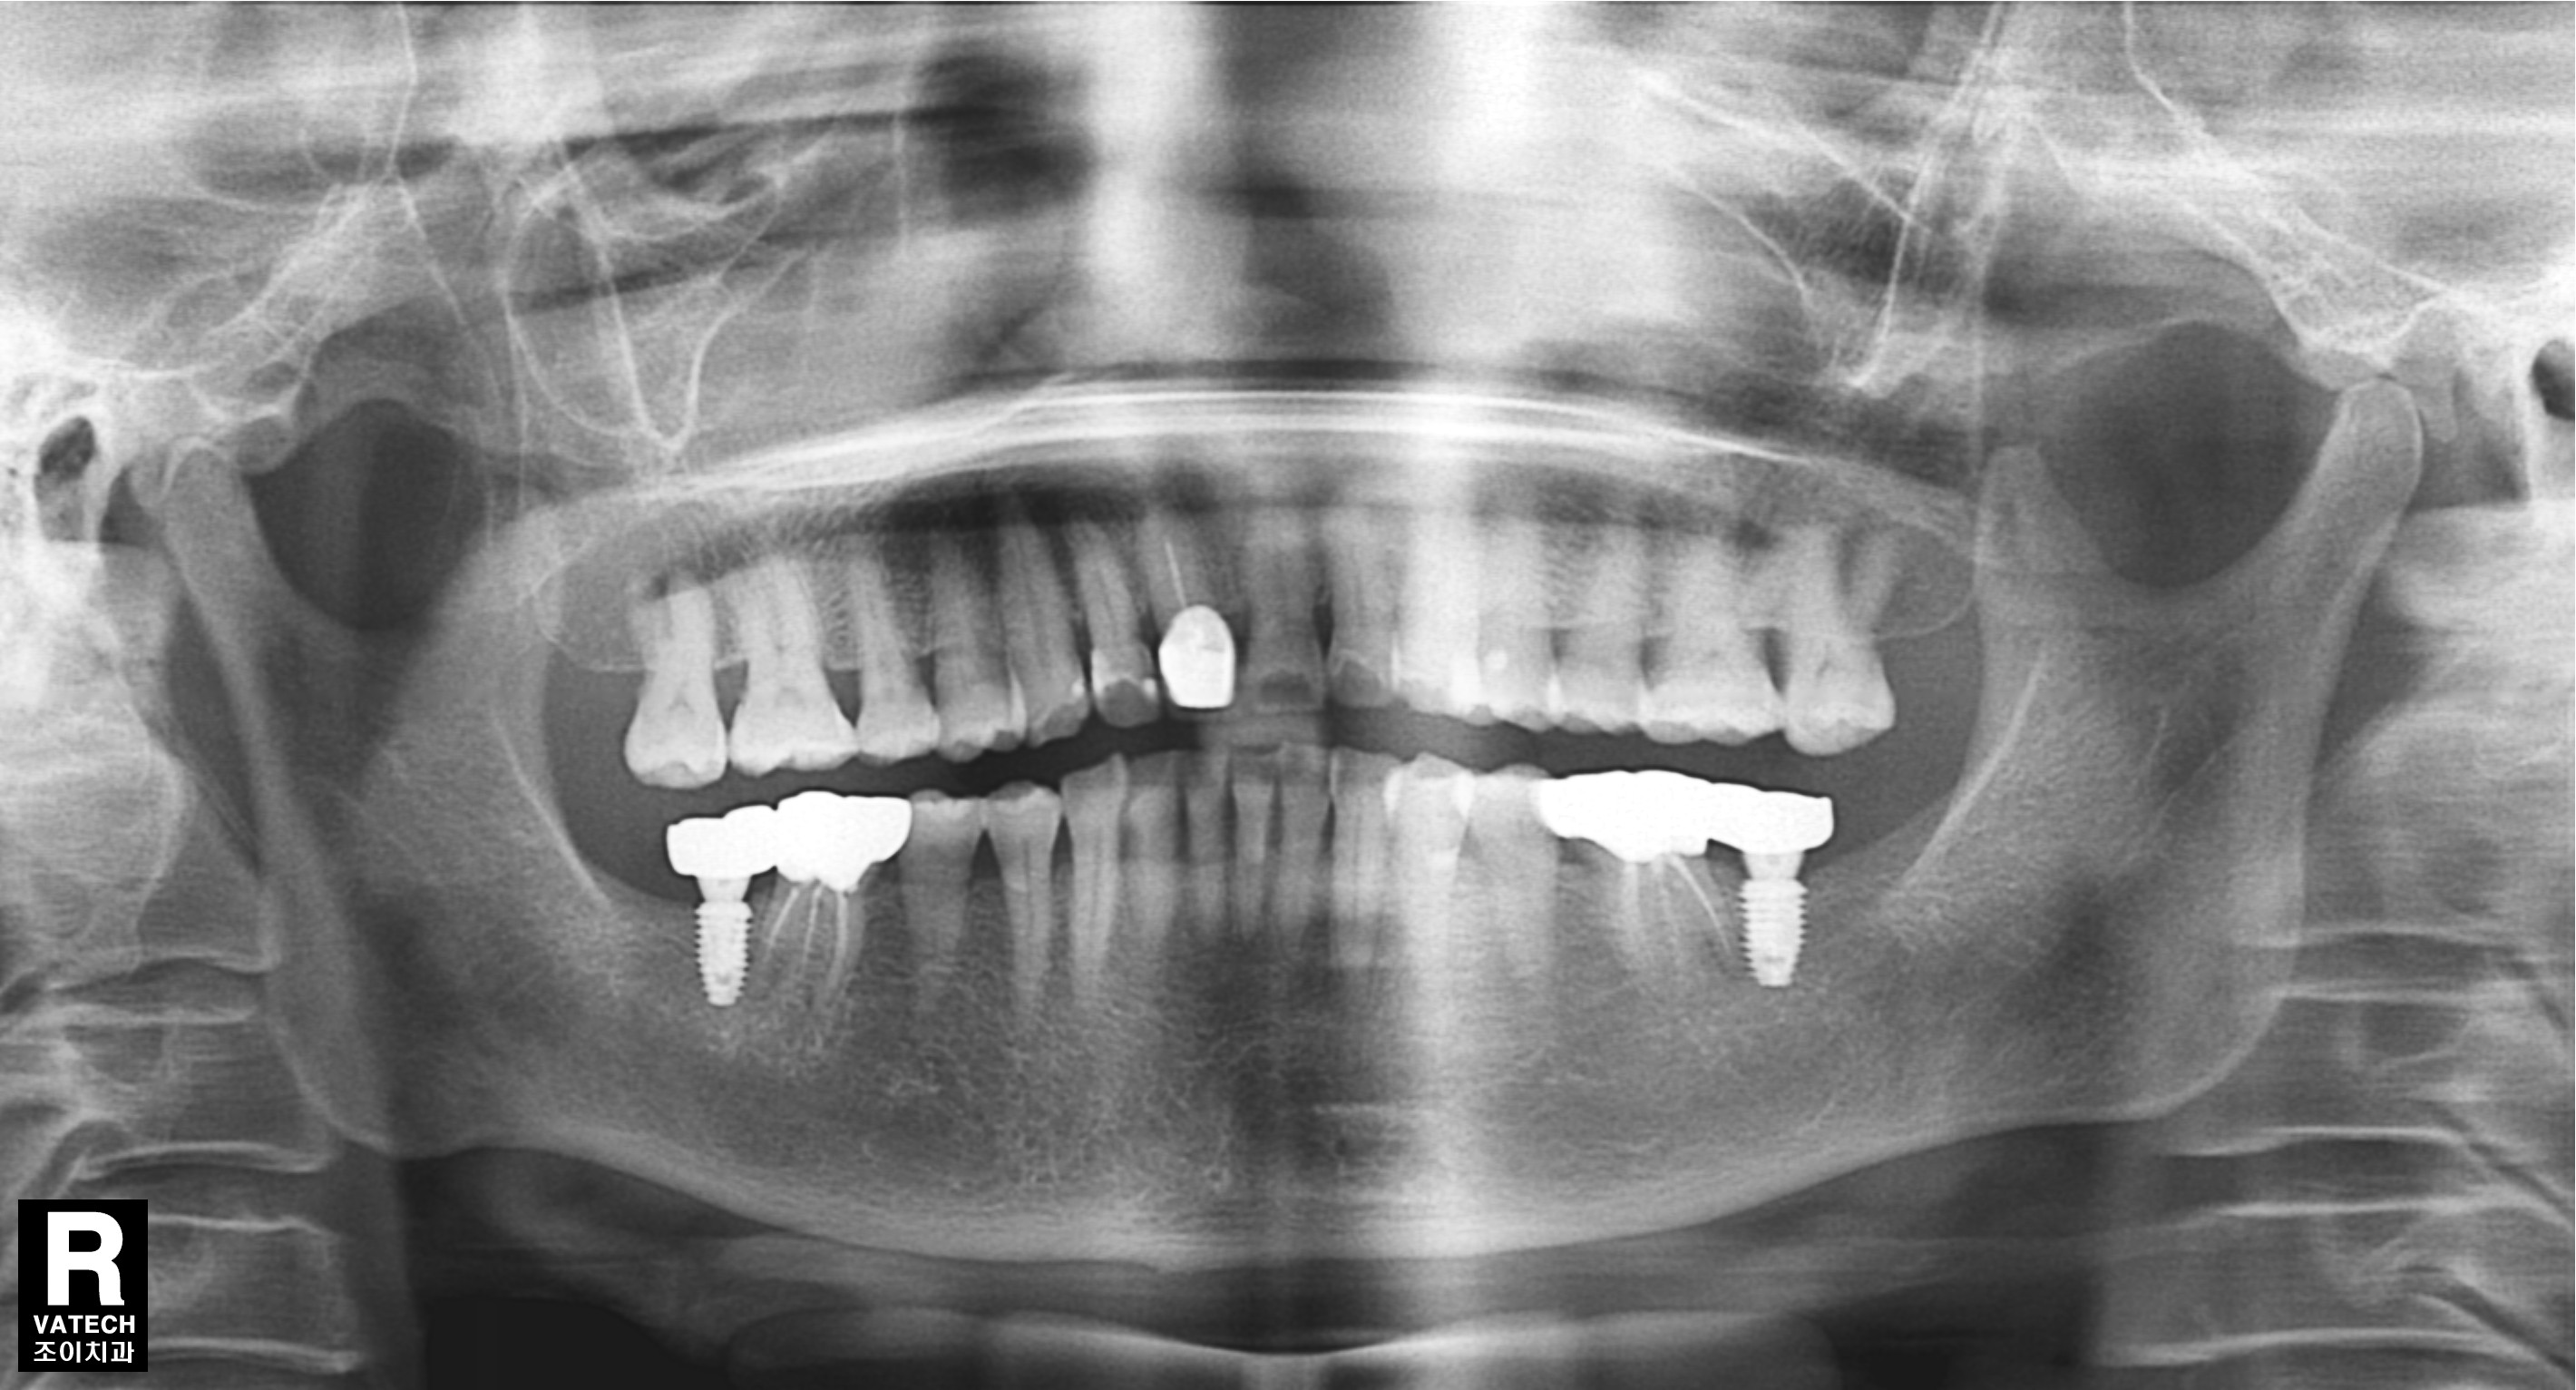

장시간 노출된 강한 교합으로 후방구치가 상실되고 그 앞니조차 뿌리에 염증이 생겨 통증이 있는 경우입니다.

상실된 치아는 임플란트로 수복하고, 염증이 생긴 치아는 근관치료와 보철치료로 수복한 증례입니다.